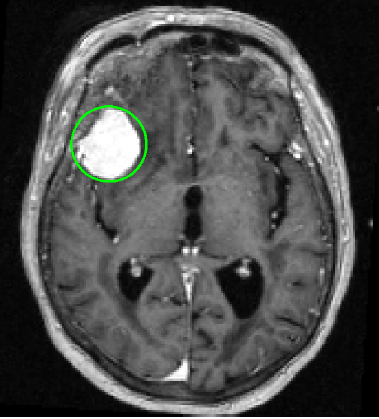

That's completely normal. What we're worried about is this area here:

2011koshy1.png